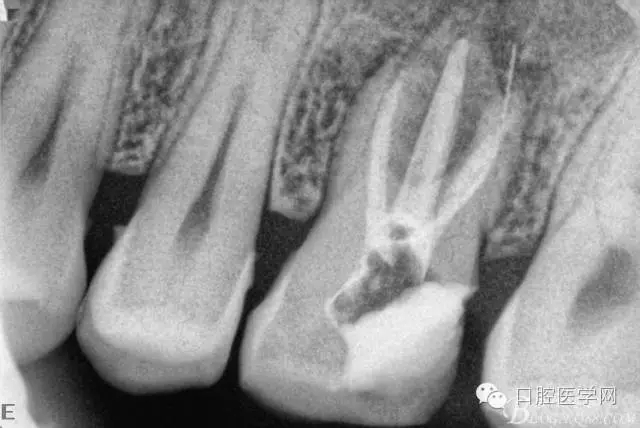

四個月后患牙Ⅰ°松動明顯好轉(zhuǎn),根管內(nèi)無異物,可行根管充填。試主尖片。

根管充填后(遠頰根內(nèi)有一斷針)。

根充后三個月。

根充后四個月。根尖炎性陰影明顯減小,唯獨遺憾的是遠頰根一斷針,不知后續(xù)如何,日后再行根尖手術(shù)吧。